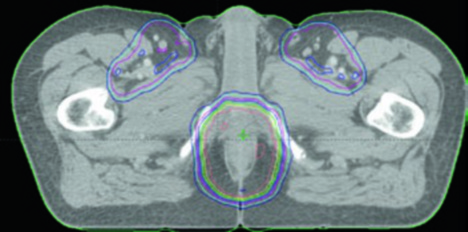

Contouring Atlas: Elective Nodal Regions

The RTOG anorectal contouring atlas describes three CTV regions that should be included for all patients with anal canal cancer. The Australasian GI Trials Group Atlas details seven elective regions. There is disagreement among the RTOG, AGITG, and BNG guidelines regarding inguinal lymph node contouring — recent data show that 10–29% of involved inguinal nodes fall outside the recommended nodal borders.

| CTV-A (perirectal, presacral, internal iliac) | Lower pelvis: inferior border 2 cm below gross disease, including entire mesorectum. Mid pelvis: rectum, mesorectum, internal iliac nodes, 1 cm margin into bladder. Upper pelvis: to the bifurcation of common iliac vessels (~sacral promontory). 7–8 mm margin around internal iliac vessels |

| CTV-B (external iliac) | Border between inguinal and external iliac at the inferior extent of the internal obturator vessels (upper edge of superior pubic rami). 7–8 mm margin, at least 1 cm anteriorly |

| CTV-C (inguinal) | Inferior extent 2 cm below the saphenous/femoral junction. Entire inguinal compartment contoured including small vessels and lymph nodes |

To adequately cover the inguinal chain, the recommended approach includes: a 2 cm radial margin around the femoral vessels, 1 cm radial margin around the saphenous/femoral junction, and 3 cm medial/lateral margin along the lower inguinal ligament. The caudal border of the inguinal CTV should be at the level of the anal margin.

| CTV-HR (high risk) | Covers CTV-P, CTV-N, entire mesorectum, perirectal nodes, and bilateral internal iliac nodes inferior to the inferior border of the sacroiliac joint. If inguinal or external iliac nodes are involved, include these regions. 0.7 cm margin around internal iliac vessels. 1.8 cm strip between external and internal iliac vessels for obturator nodes. 1–1.5 cm anteriorly into bladder |

| CTV-LR (low risk) | Covers uninvolved internal iliac nodes superior to the sacroiliac joint inferior border, plus uninvolved external iliac and inguinal nodes. Margins: 0.7 cm around internal iliac vessels; 1 cm anterolateral on external iliacs; entire inguinal compartment contoured |